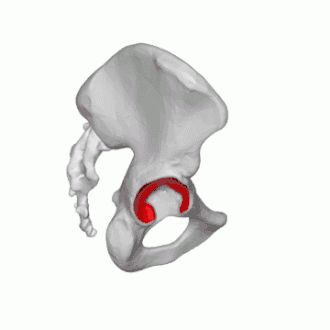

Ces fractures sont divisées en deux types : les fractures de la ceinture pelvienne (dites fractures pelviennes ou du pelvis) qui ne touchent pas l'articulation coxale, et les fractures du cotyle (dites acétabulaires) où un trait de fracture passe par la surface articulaire de l'os coxal. Ces deux types de fractures peuvent être stables ou instables.

Fractures du cotyle

Les fractures du cotyle peuvent résulter d’un choc sur la région trochantérienne (bord externe de la hanche), la tête fémorale est alors poussée dans le bassin (chute sur le trochanter, de sa hauteur pour la personne âgée, chute de plus grande hauteur pour le sujet jeune)[8],[12].

Elles peuvent aussi résulter d’un choc dans l’axe du fémur : typiquement lors d'un accident de voiture où le genou du conducteur vient heurter le tableau de bord, provoquant une luxation postérieure de hanche avec fracture du rebord postérieur du cotyle. Ce type de lésion, survenant sur le sujet jeune par accident à haute énergie cinétique, a été réduit de façon significative par l'obligation de porter la ceinture de sécurité[12].

Les fractures du cotyle dépendent de la classification de Judet-Letournel, établie en 1964, et qui reste le gold standard au XXIe siècle[12].

Dans cette classification, l'os iliaque est considéré comme formé de deux colonnes : l'une antérieure ou ilio-pubienne, l'autre postérieure ou ilio-ischiatique, réunies par une clé de voûte : le toit du cotyle.

Les fractures du cotyle sont alors classées en dix catégories réparties en deux groupes (fractures élémentaires et fractures complexes) :

- Les fractures élémentaires concernent une seule colonne, antérieure ou postérieure, elles sont souvent associées à une luxation de hanche. Les auteurs en distinguent cinq : fracture du rebord postérieur, de la colonne postérieure, de la paroi antérieure, de la colonne antérieure, et la fracture transversale.

- Les fractures mixtes ou complexes, associant deux ou plusieurs fractures élémentaires, avec fracture des deux colonnes, décrites aussi en cinq variétés[12].